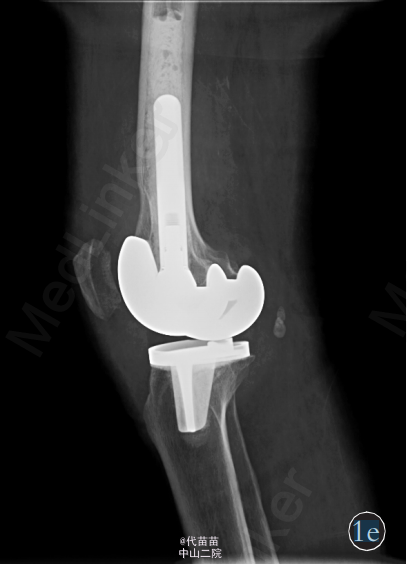

患者,女,70岁 。主因右膝关节间断性疼痛4年,加重2个月入院。患者自诉4年前无明显诱因出现膝关节间断性疼痛,活动时疼痛加重,休息后症状缓解,同时伴有右膝关节肿胀,膝关节活动时弹响症状明显,无夜间痛,未系统治疗。近2个月来患者疼痛症状逐渐加重,不能完全蹲下,并出现右小腿轻度肿胀。患者既往体健。查体:右膝关节肿胀,无发红及包块。右膝关节间隙按压痛阳性,浮髌试验阳性,髌骨摩擦试验阳性,右膝关节活动度:0°~130°,右下肢肌力Ⅳ级,其他检查未见异常。 影像学检查:X 线片示右侧膝关节不对称性变窄,关节面硬化,边缘可见唇样骨质增生,股骨下端凹槽样改变,边界较清楚,无骨膜反应,髌骨呈槽沟样改变(图 1a)。 右膝关节 CT 示右侧髌骨较薄,髌骨关节面锯齿样改变(图 1b)。MRI检查示膝关节腔内液体增多髌上囊内可见低信号影(图 1c)。为排除肿瘤及感染的可能性,进一步行实验室检查:血常规、ESR、CRP 及碱性磷酸酶以及 ECG 检查均未见异常。完善相关检查后, 择期行全膝关节表面置换术及滑膜清理术。为防止术后股骨缺损处出现病理性骨折,考虑选用制定型膝关节假体(股骨假体柄加长)。术中见:膝关节髌上囊内有大量陈旧性积血(图 1d),滑膜增生肥厚,股骨远端髁部上段可见轮廓清楚的凹陷性骨侵蚀面,股骨及胫骨骨赘形成,股骨髁及胫骨平台关节面软骨破坏,股骨外侧髁破坏严重,部分软骨下骨外露, 髌骨外侧变薄, 髌骨关节面有沟槽样凸凹不平(图1d),软骨面破坏,外侧较重,软骨下骨外露。 术中将病变关节囊及滑膜送检病理,快速病理回报:色素绒毛结节性滑膜炎可能性大。 术中彻底切除髌上囊、滑膜、髌下脂肪垫及半月板,切除胫骨表面、前十字韧带及后十字韧带,处理股骨髁,矫正 FTA 角为外翻 5°,安装 Depuy 公司 2 号股骨假体加长柄及2 号胫骨假体,胫骨假体上安装 8 mm 垫片,复位关节。检查内外侧软组织平衡良好,功能活动良好,此时行髌骨成形术,修理髌骨后见髌骨活动轨迹差, 缝合前向关节腔内软组织注入镇痛药物。 术后右侧膝关节侧位片示:假体固定位置良好,股骨加长柄通过股骨皮质缺损区(图 1e)。 术后病理诊断:色素绒毛结节性滑膜炎(图 1f)。 术后 24 h 拔除负压引流,伸直位

鉴于本例患者合并严重膝关节面和髌骨关节面破坏 ,以及股骨干下段髁上前侧骨皮质缺损, 因此选择全膝关节表面置换术、全膝滑膜清理术。 由于普通股骨假体的柄较短,股骨磨损区正位于假体与正常骨质交汇处, 而股骨下段磨损区骨皮质较正常骨质薄,发生骨折的几率较正常高,因此在股骨侧假体选择上,选用加长柄股骨假体,减少股骨下段骨磨损区应力,降低骨折风险性。 本例患者术后膝关节功能良好,疼痛症状明显好转,无复发,效果好。治疗不足之处:考虑到患者髌骨较薄,无法行髌骨置换术,因此患者只行髌骨修理术,修理后的髌骨关节面仍不光滑且呈凹陷状,因此术后髌骨轨迹差。